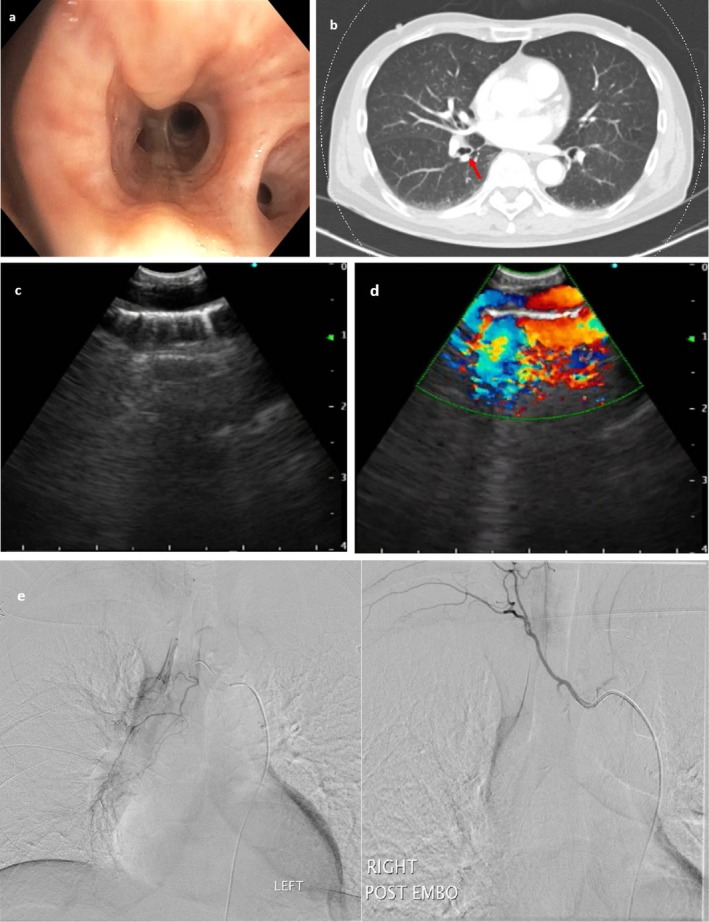

We report a case of bronchial Dieulafoy presenting with haemoptysis, initially resembling an endobronchial tumour on bronchoscopy. This case highlights the critical role of EBUS in the assessment of suspicious endobronchial lesions and in preventing potentially life-threatening complications from inadvertent biopsy.